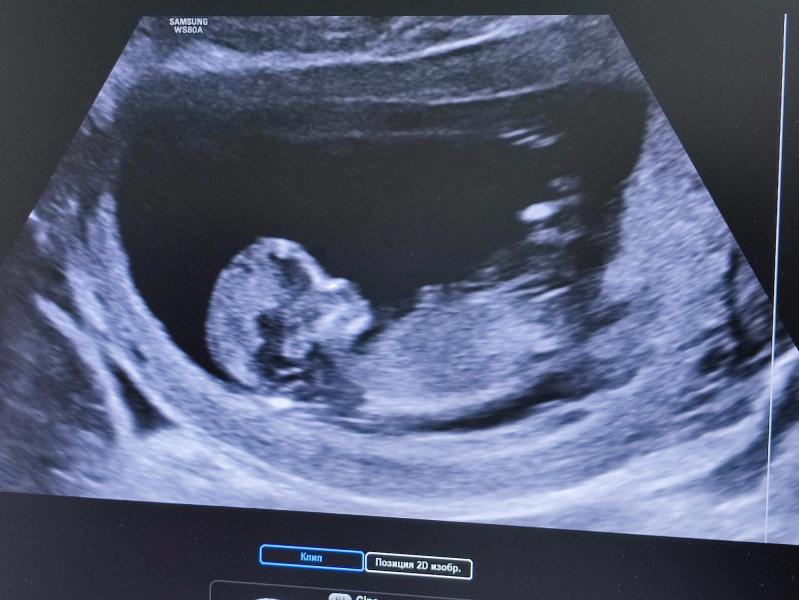

Сегодня малышу 12 недель. Прошла первый скрининг, все хорошо. Токзикоз уменьшился, но не прошел. Очень чувствительна к запахам 🤢